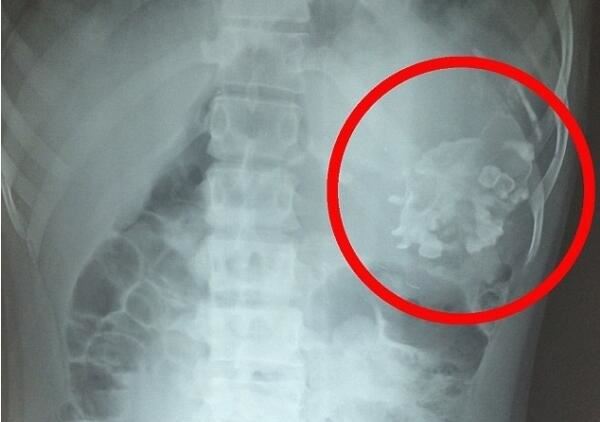

库玛到医院做了X光检查,发现他的肚子里有个异物,令所有人都想不到的是,那个异物竟然是他的双胞胎弟弟!他已经寄生在库玛的肚子里18年了。

最后医生手术将库玛的双胞胎弟弟取出,更加惊人的是库玛的弟弟在他体内一直活着!

他吸收库玛的养分才得以存活,身体也不断成长,但他只有发育不良的头、胸、脊骨等等的不完全的身体结构,加上毛发和牙齿,总共重2.5公斤,全身加上头发有20多厘米长了。